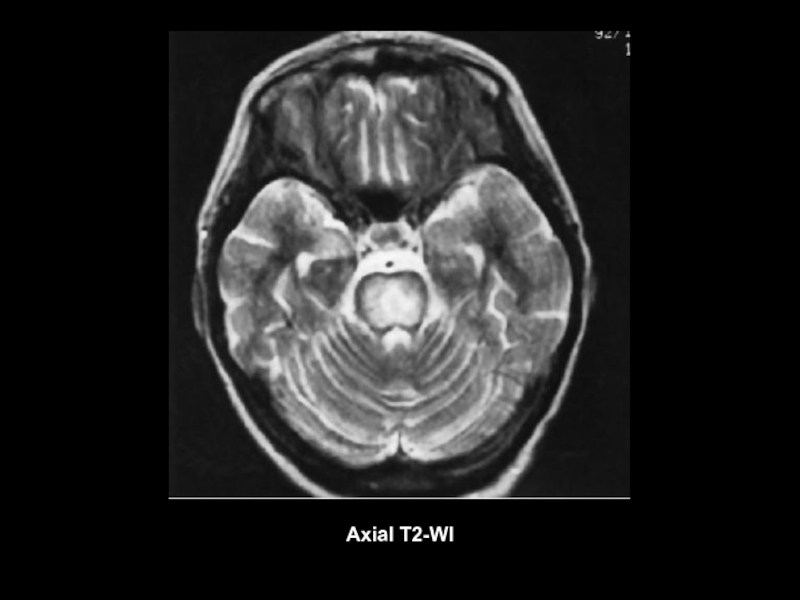

Axial T2-WI

Слайд 27Центральный понтинный и экстрапонтиный миелинолиз

Осмотический демиелинизирующий синдром (понтийный и экстрапонтийный

миелинолиз)

- форма демиелинизирующего поражения головного мозга, которая

развивается на фоне метаболических нарушений водно-солевого обмена.

В случае развития демиелинизирующего процесса в области моста головного мозга

говорят о центральном понтийном миелинолизе. Также, изолированно или в

сочетании с ЦПМ, может наблюдаться экстрапонтийный миелинолиз, при

котором очаги демиелинизации могут обнаруживаться в ножках мозга, таламусе,

мозолистом теле и др. церебральных структурах.